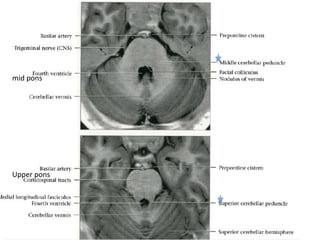

mid	pons

Upper	pons

Trigeminal	nerve	CNS	is	seen	as	it	courses	toward	Meckel	cave.

Dentate	nucleus	is	only	cerebellar	nucleus	that	is	seen	on	imaging

The pons comprises a bulbous convexity anteriorly, the basis pontis,

The posterior part of the pons, the pontine tegmentum, forms the floor

of the upper part of the fourth ventricle, and contains cranial

nerve nuclei (V, VI, VII, VIII).